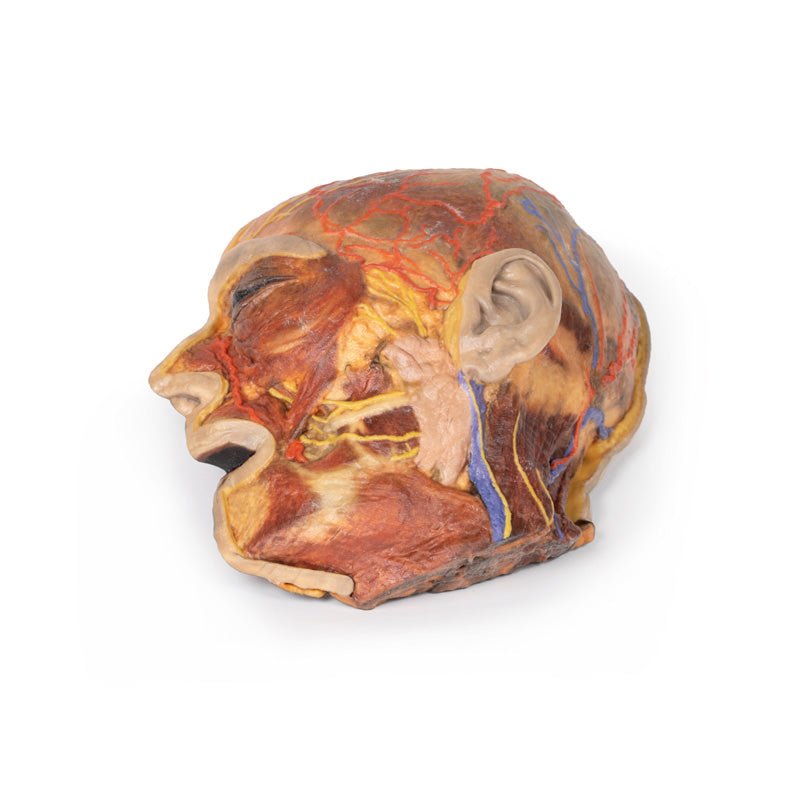

3D Printed Superficial Facial Nerves & Parotid Gland

This 3D model presents the superficial anatomy of the face and head, and compliments the superficial facial anatomy

of our HW 44 model with a more expanded dissection across the scalp and occipital regions.

The superficial

neurovascular and muscular structures in the face largely mirror the structures described in reference to our HW 44

specimen (see description), although the terminal branches of the facial nerve (CNVII) can be largely followed

across a longer course from the parotid gland and the platysma muscle has been retained superficial to the mandible

and extends towards the neck.

In contrast to the HW 44 specimen, this model has a more expansive superficial

dissection inferior to the external ear and across the posterior scalp and occipital region. This allows for an

expanded appreciation of the neurovascular distribution of the supraorbital and supratrochlear nerves and arties

with the superficial temporal artery. Inferior to the ear, the retromandibular vein has been exposed with the

ascending fibres of the great auricular nerve on its superficial surface (and further branches of this nerve on the

surface of the sternocleidomastoid muscle). At the posterior border of the sternocleidomastoid muscle the lesser

occipital nerve is just preserved, near the exiting and ascension of the occipital artery and vein near the

trapezius muscle towards the posterior scalp. Surrounding the external ear are fibres of the auricularis superior

and posterior muscles. Near the margin of the dissection window posteriorly the deep fibres of the occiptalis muscle

can be seen integrated into the epicranius (occipitofrontalis) muscle.